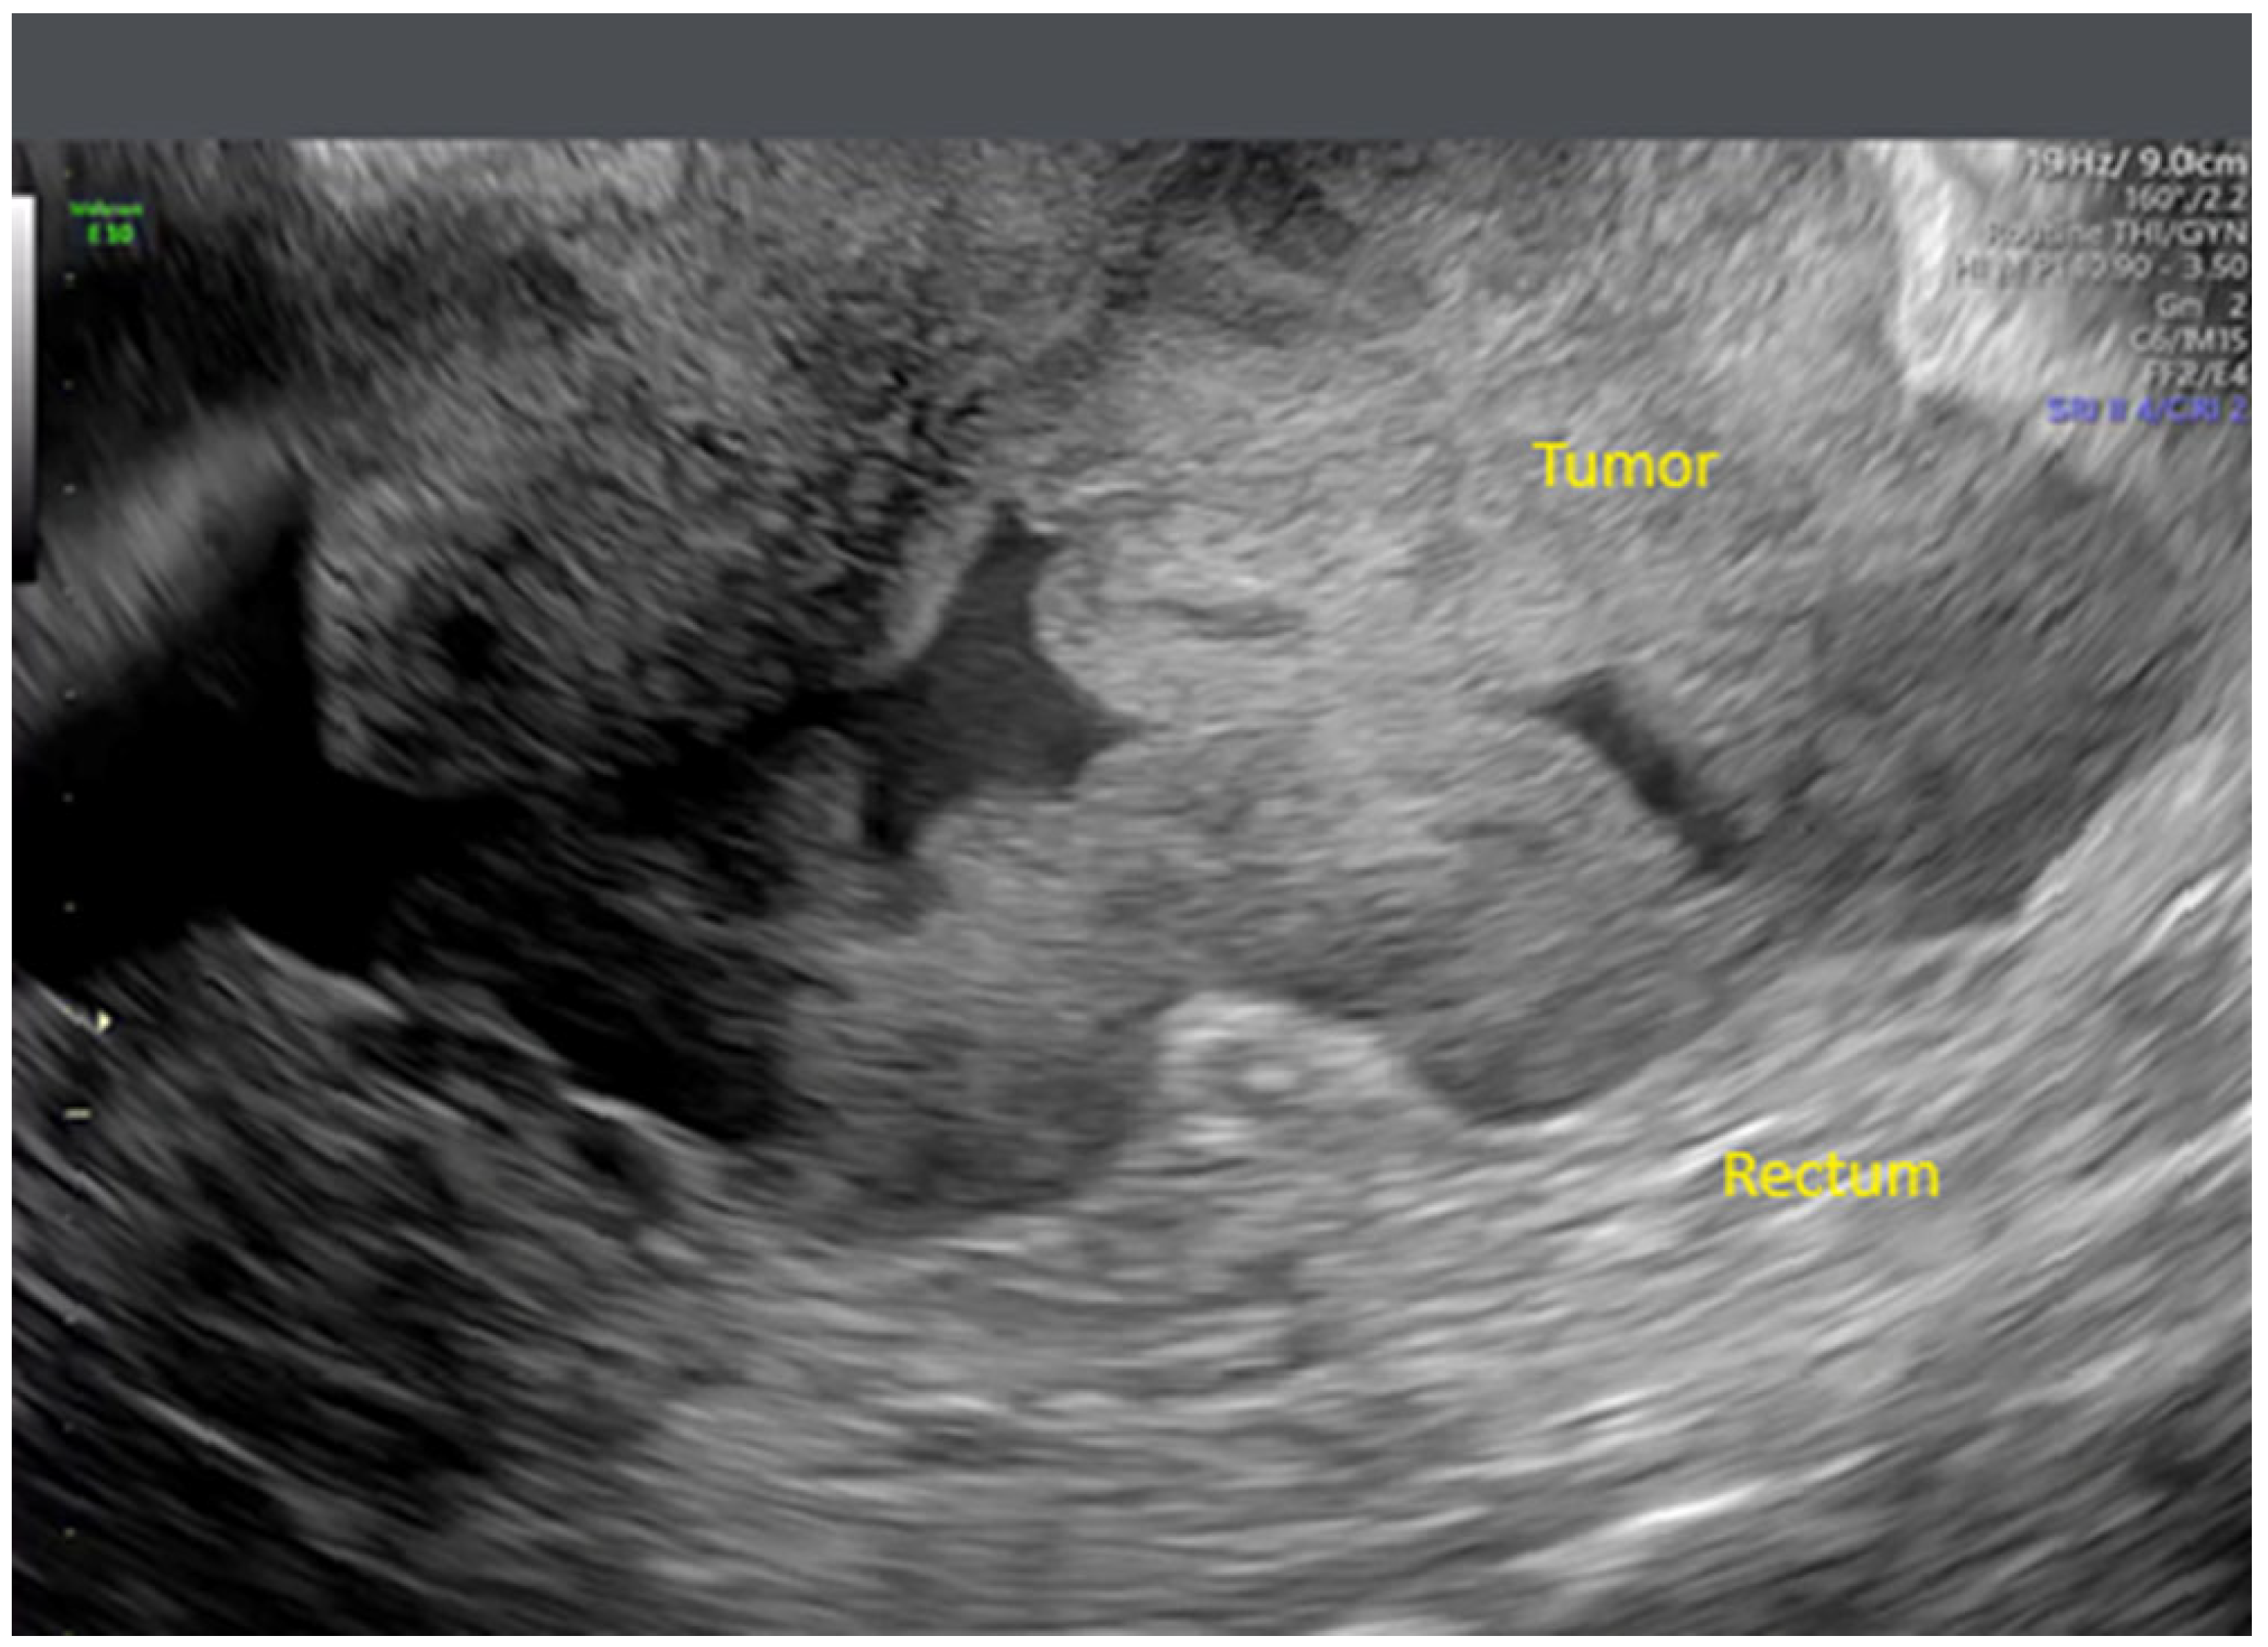

- Zikan, M.; Fischerova, D.; Semeradova, I.; Slama, J.; Dundr, P.; Weinberger, V.; Dusek, L.; Cibula, D. Accuracy of ultrasound in prediction of rectosigmoid infiltration in epithelial ovarian cancer. Ultrasound Obstet. Gynecol. 2017, 50, 533–538. [Google Scholar] [CrossRef]

- Fischerova, D. Ultrasound scanning of the pelvis and abdomen for staging of gynecological tumors: A review. Ultrasound Obstet. Gynecol. 2011, 38, 246–266. [Google Scholar] [CrossRef]

- Fischerova, D.; Zikan, M.; Semeradova, I.; Slama, J.; Kocian, R.; Dundr, P.; Nemejcova, K.; Burgetova, A.; Dusek, L.; Cibula, D. Ultrasound in preoperative assessment of pelvic and abdominal spread in patients with ovarian cancer: A prospective study. Ultrasound Obstet. Gynecol. 2017, 49, 263–274. [Google Scholar] [CrossRef]